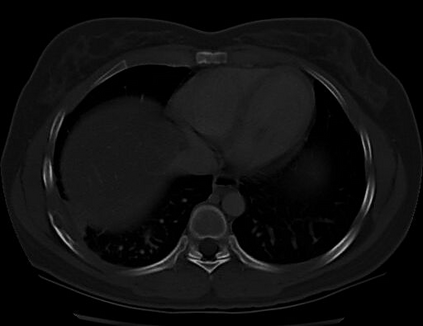

The evaluation of infectious disease processes on radiologic images is an important and challenging task in medical image analysis. Pulmonary infections can often be best imaged and evaluated through computed tomography (CT) scans, which are often not available in low-resource environments and difficult to obtain for critically ill patients. On the other hand, X-ray, a different type of imaging procedure, is inexpensive, often available at the bedside and more widely available, but offers a simpler, two dimensional image. We show that by relying on a model that learns to generate CT images from X-rays synthetically, we can improve the automatic disease classification accuracy and provide clinicians with a different look at the pulmonary disease process. Specifically, we investigate Tuberculosis (TB), a deadly bacterial infectious disease that predominantly affects the lungs, but also other organ systems. We show that relying on synthetically generated CT improves TB identification by 7.50% and distinguishes TB properties up to 12.16% better than the X-ray baseline.